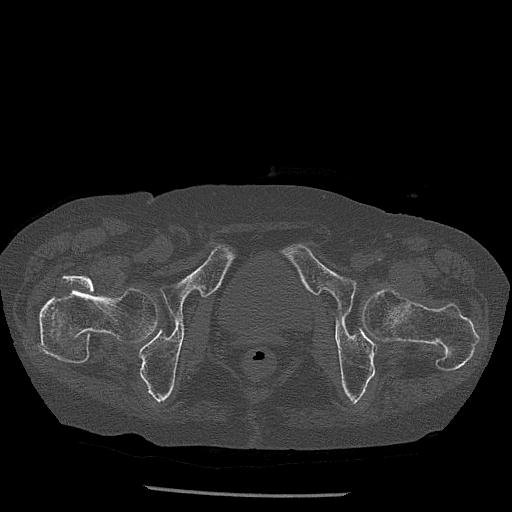

100703 1/27 両股正面+軸 1/29 両股正面+軸 94歳女性 パンソンロン